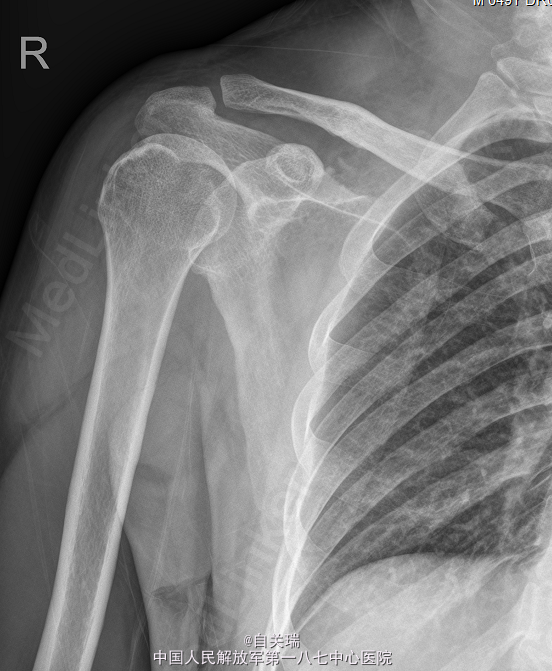

右肩胛骨冈上方可触及一肿块,大小约2*3cm,局部压痛(+),皮色皮温正常,右肩活动正常,末梢血供及感觉功能存在。MRI提示:右肩胛冈上缘占位,骨软骨瘤可能。

初步诊断:右肩胛骨肿瘤. 在全麻下行右肩胛骨软骨瘤切除术. 取右肩胛骨沿肩胛冈横行切口,约8cm切口,分离达右肩胛骨见约5*4cm大小,质硬肿瘤组织,与肩胛骨关系紧密,可见软骨帽及纤维膜,予以仔细分离,凿除肿瘤及部分肩胛骨组织.

术程顺利,给予注射用头孢呋辛钠(安可欣) 1.5g 静滴 二次/日及输液支持治疗。放射检查(右上肢)检查提示:右肩胛骨术后改变。